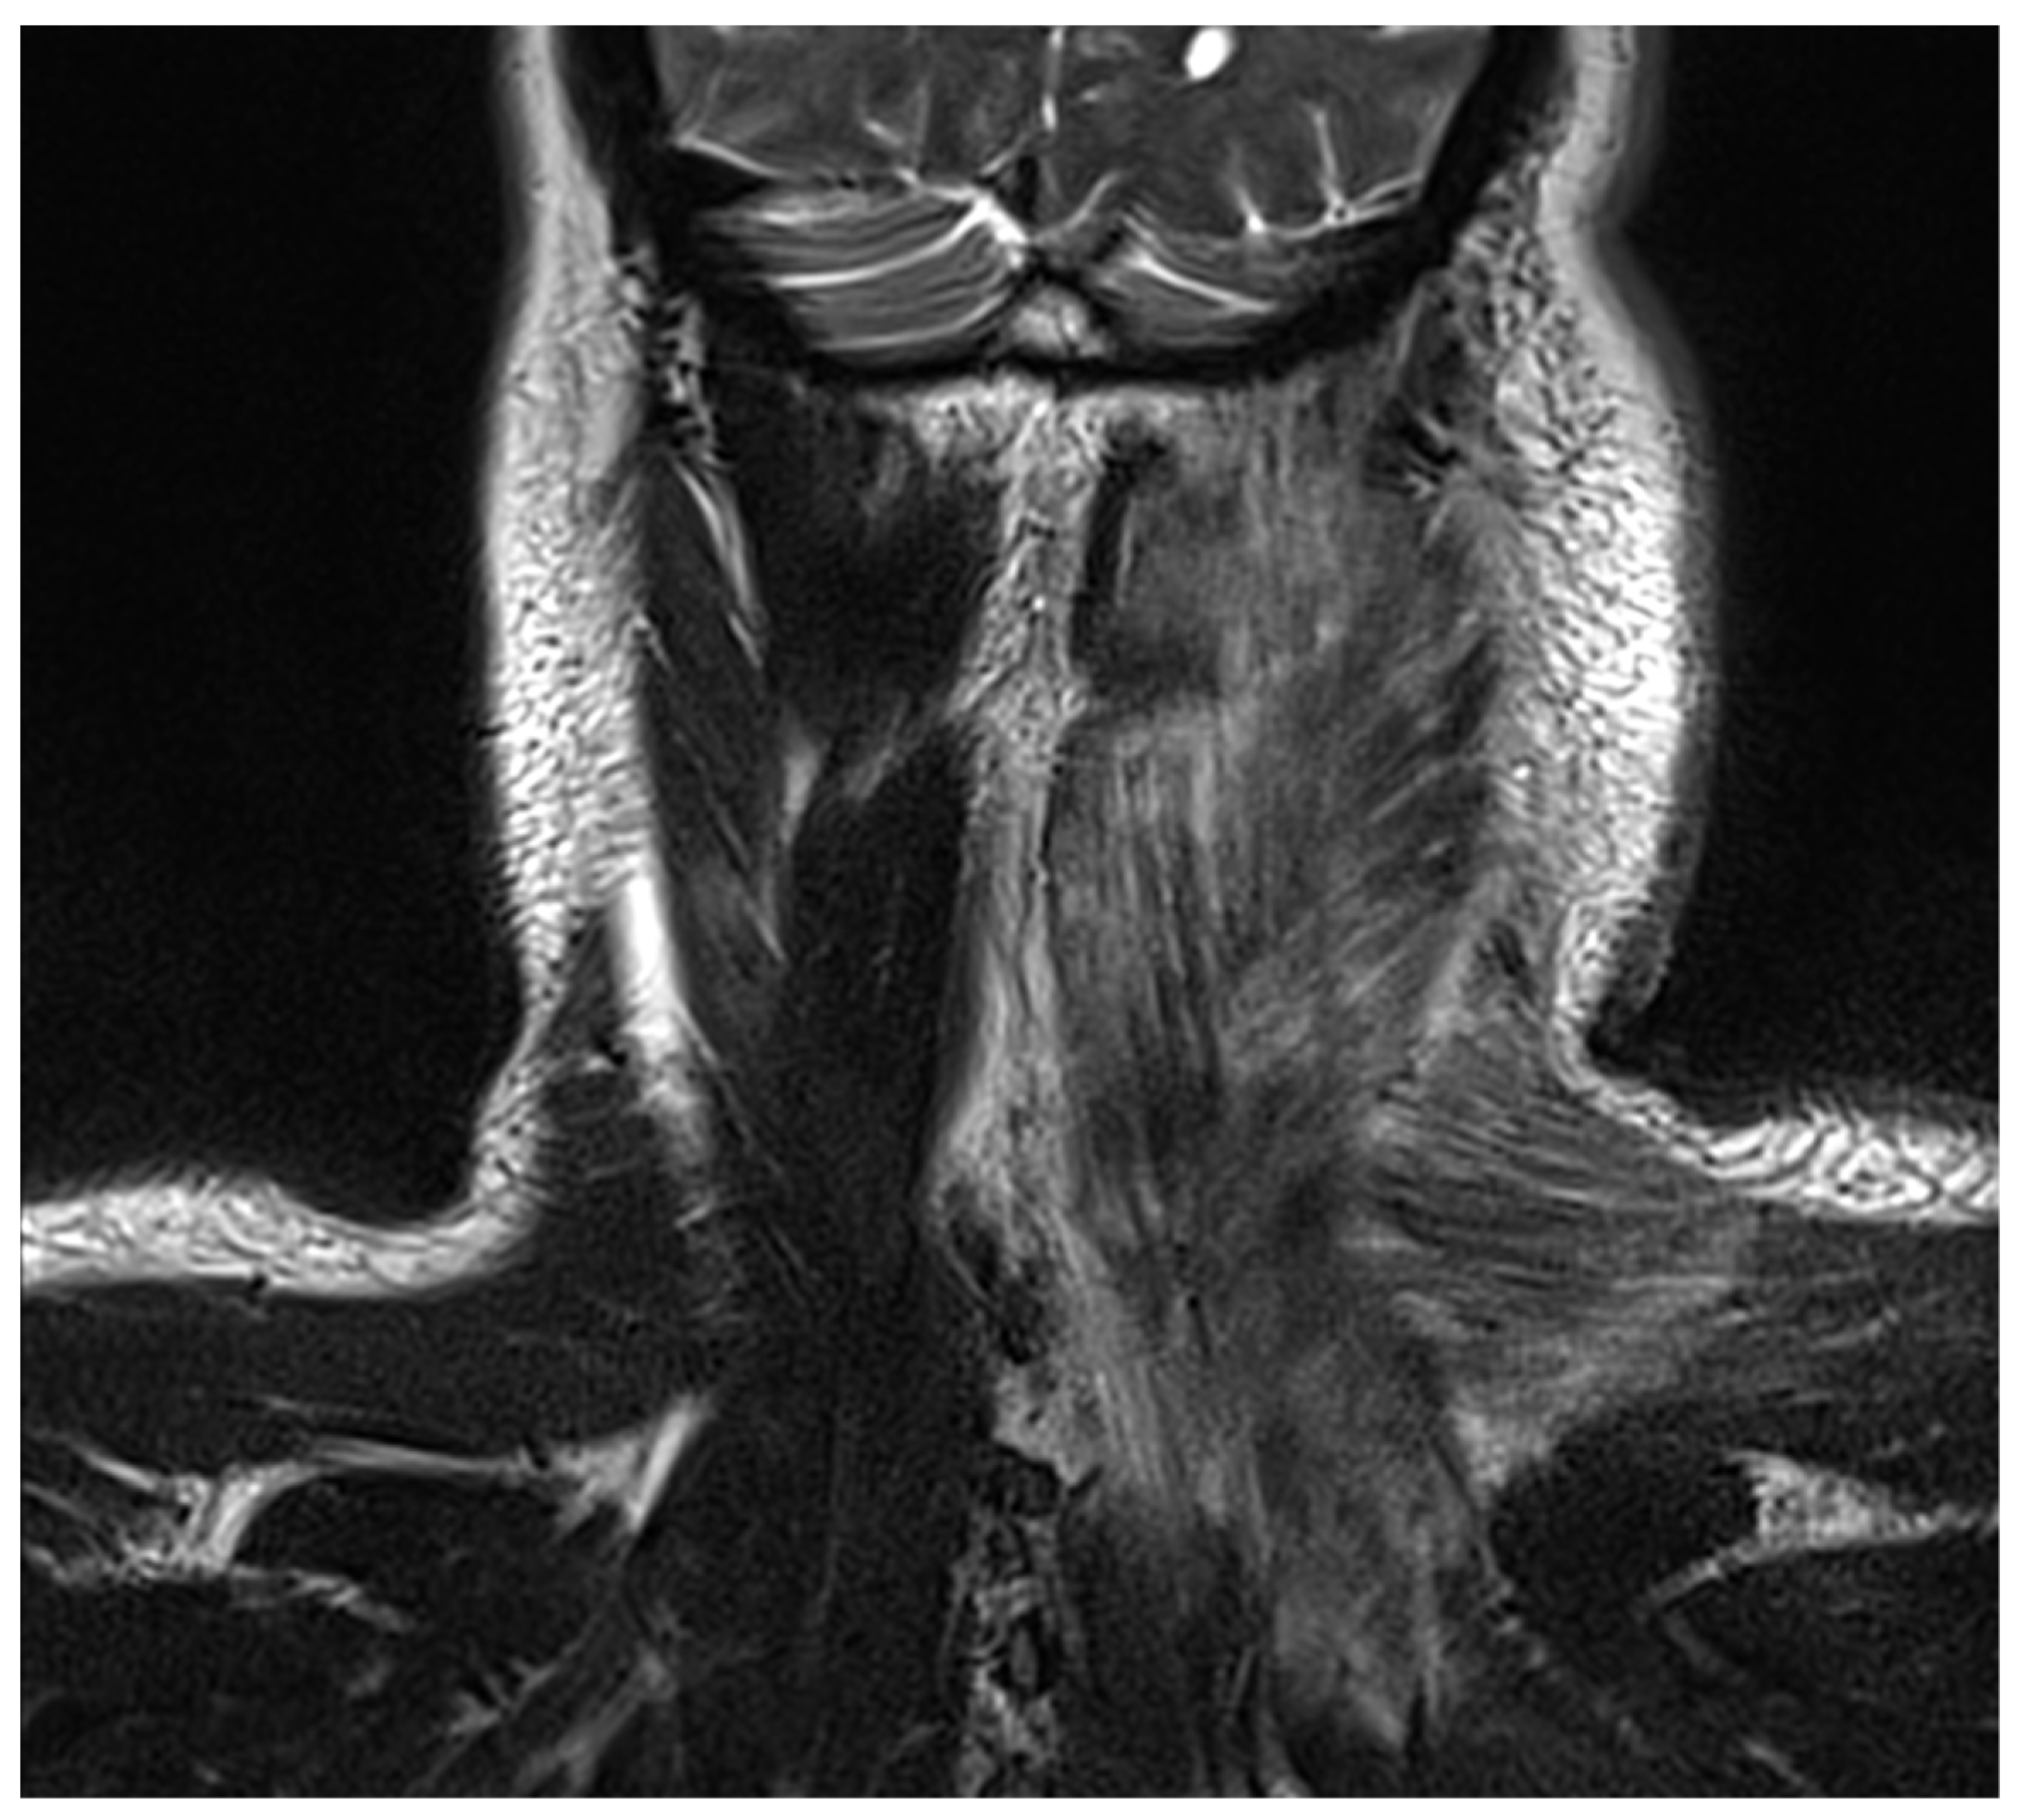

Preoperative radiographic images of two patients with DNM showing signs of neck and mediastinal involvement are shown in Figure 1 and Figure 2.

Figure 1.

Cervical MRI image showing a neck abscess in a 44-year-old patient with DNM, treated with right cervicotomy and VATS mediastinal drainage.